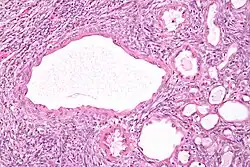

| Micrograph of a cystic nephroma (left of image). Normal kidney is seen on the right. H&E stain. | |

A cystic nephroma, also known as multilocular cystic nephroma, mixed epithelial stromal tumour (MEST) and renal epithelial stromal tumour (REST),[1] is a type of rare benign kidney tumour.